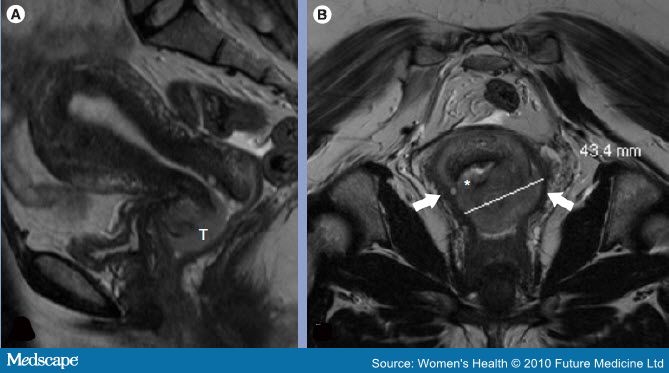

КТ и МРТ

Определение рака шейки матки возможно при использовании дополнительных методах исследования. Специалисты чаще назначают МРТ, результаты этого исследования четко показывают, насколько распространен онкологический процесс. Также оценивается состояние соседних органов. Благодаря этому врач назначает необходимое лечение.

У КТ есть недостаток – она показывает примерно одинаковую плотность органов малого таза. Это может стать причиной того, что раковое новообразование может быть названо жировой тканью. Если это происходит, то специалист и пациентка теряют время, необходимое для лечения патологии.